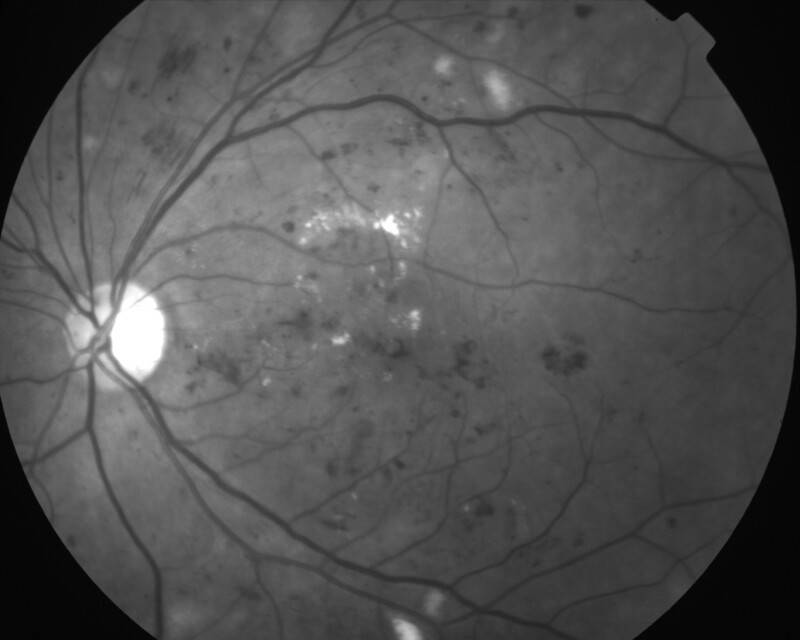

RETINOPATHIE DIABETIQUE NON PROLIFERANTE SEVERE

IMG0001.JPG